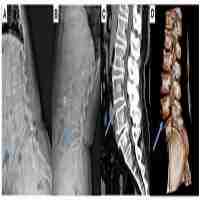

| Abstract | Background Utilization of a cage with a large footprint in lateral lumbar interbody fusion (LLIF) for the treatment of spondylolisthesis leads to a high fusion rate and neurological improvement owing to the indirect decompression effect and excellent alignment correction. However, if an interbody space is too narrow for insertion of an LLIF cage for cases of spondylolisthesis of Meyerding grade II or higher, LLIF cannot be used. Therefore, we developed a novel strategy, LLIF after reduction by the percutaneous pedicle screw (PPS) insertion system in the lateral position (LIFARL), for surgeons to perform accurate and safe LLIF with PPS in patients with such pathology. This study aimed to introduce the new surgical strategy and to present preliminary clinical and radiological results of patients with spondylolisthesis of Meyerding grade II. Methods Six consecutive patients (four men and two women; mean age, 72.7 years-old; mean follow-up period, 15.3 months) with L4 spondylolisthesis of Meyerding grade II were included. Regarding the surgical procedure, first, PPSs were inserted into the L4 and L5 vertebrae fluoroscopically, and both rods were placed in the lateral position. The L5 set screws were fixed tightly, and the L4 side of the rod was floated. Second, the L4 vertebra was reduced by fastening the L4 set screws so that they expanded the anteroposterior width of the interbody space. At that time, the L4 set screws were not fully tightened to the rods to prevent the endplate injury. Finally, the LLIF procedure was started. After inserting the cage, a compression force was added to the PPSs, and the L4 set screws were completely fastened. Results The mean operative time was 183 min, and the mean blood loss was 90.8 mL. All cages were positioned properly. Visual analog scale score and Oswestry disability index improved postoperatively. Bone union was observed using computed tomography 12 months after surgery. Conclusion For cases with difficulty in LLIF cage insertion for Meyerding grade II spondylolisthesis due to the narrow anteroposterior width of interbody space, LIFARL is an option to achieve LLIF combined with posterior PPS accurately and safely. Trial registration UMIN-Clinical Trials Registry, UMIN000040268, Registered 29 April 2020, https://upload.umin.ac.jp/cgi-open-bin/ctr/ctr_view.cgi?recptno=R000045938 |